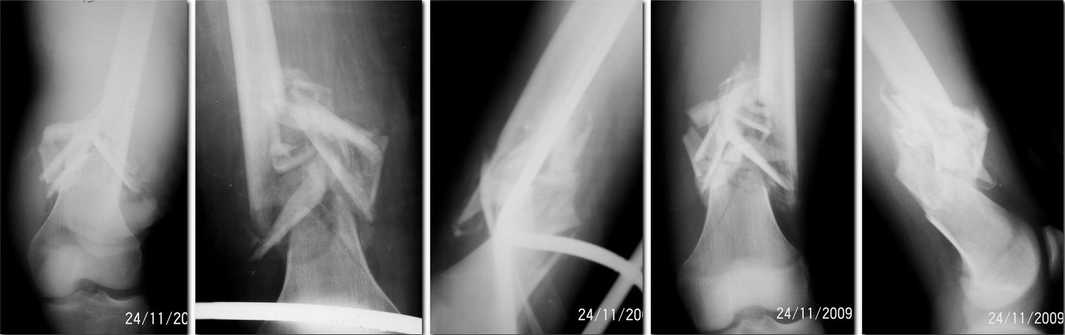

Re: застарелый открытый многооскольчатый перелом бедренной кости

Тони 28 Ноябрь 2009, 00:23

Отправитель: Николов Олег 29 Ноябрь 2009, 21:52

Всеж на наш взгляд укорочение конечности и плонтость свежей костной мозоли не выглядят катастрофическими. Будем пытаться одномоментно скоррегировать.

А опыт введения антеградных штифтов с короткими дистальными фрагментами бедренной кости в застарелых случаях у нас небольшой и всегда большие трудности с репозицией-манипулированием дистальным отломком. На мой взляд манипулировать таки легче на штифте с провизорными шилами-винтами...